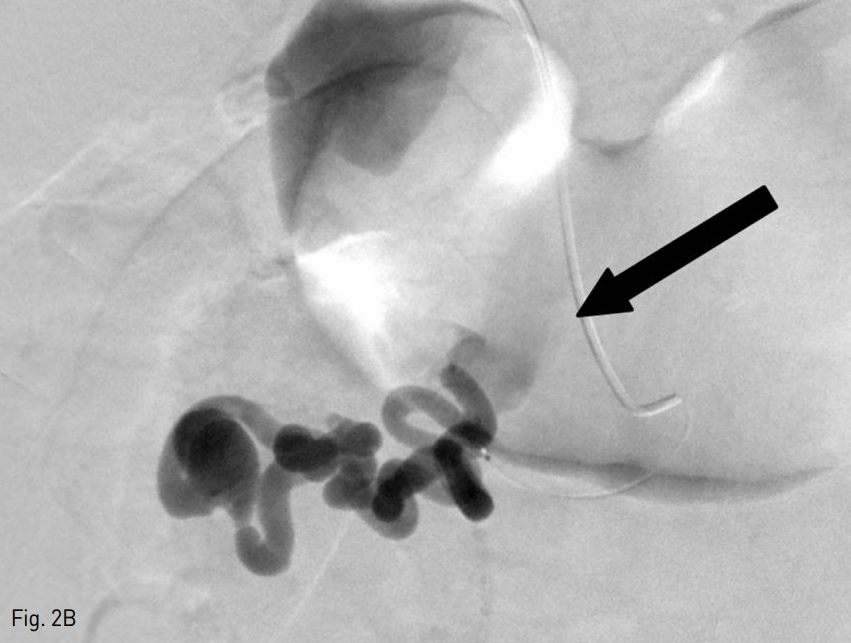

Fig. 2

A. Initial portogram shows duodenal varices with two feeding vessels and cystic dilatation

B. After superselection for inferior feeding vessel, portogram shows duodenal varices with portosystemic shunt, via right renal vein (black arrow).

초음파 유도하 우측 간문맥을 천자하여 5 Fr sheath (Terumo, Tokyo, Japan)를 삽입하였고, pig-tail catheter (Cook, Bloomington, USA)을 이용하여 시행한 간문맥 조영술 시행하였다. 간문맥 조영술상 최대 직경 2cm의 낭성 확장 및 두 개의 영양혈관을 가진 정맥류가 확인되었다 (Fig. 2A). 이후 5 Fr cobra catheter (Terumo, Tokyo, Japan) 및 2.2 Fr microcatheter (Progreat; Terumo, Tokyo, Japan)을 이용하여 아래쪽 영향혈관을 초선택 하였고, 시행한 조영술 상 오른쪽 신정맥을 경유하여 하부대정맥으로 배액되는 문맥전신단락 (portosyste mic shunt)도 확인되었다 (Fig. 2B).